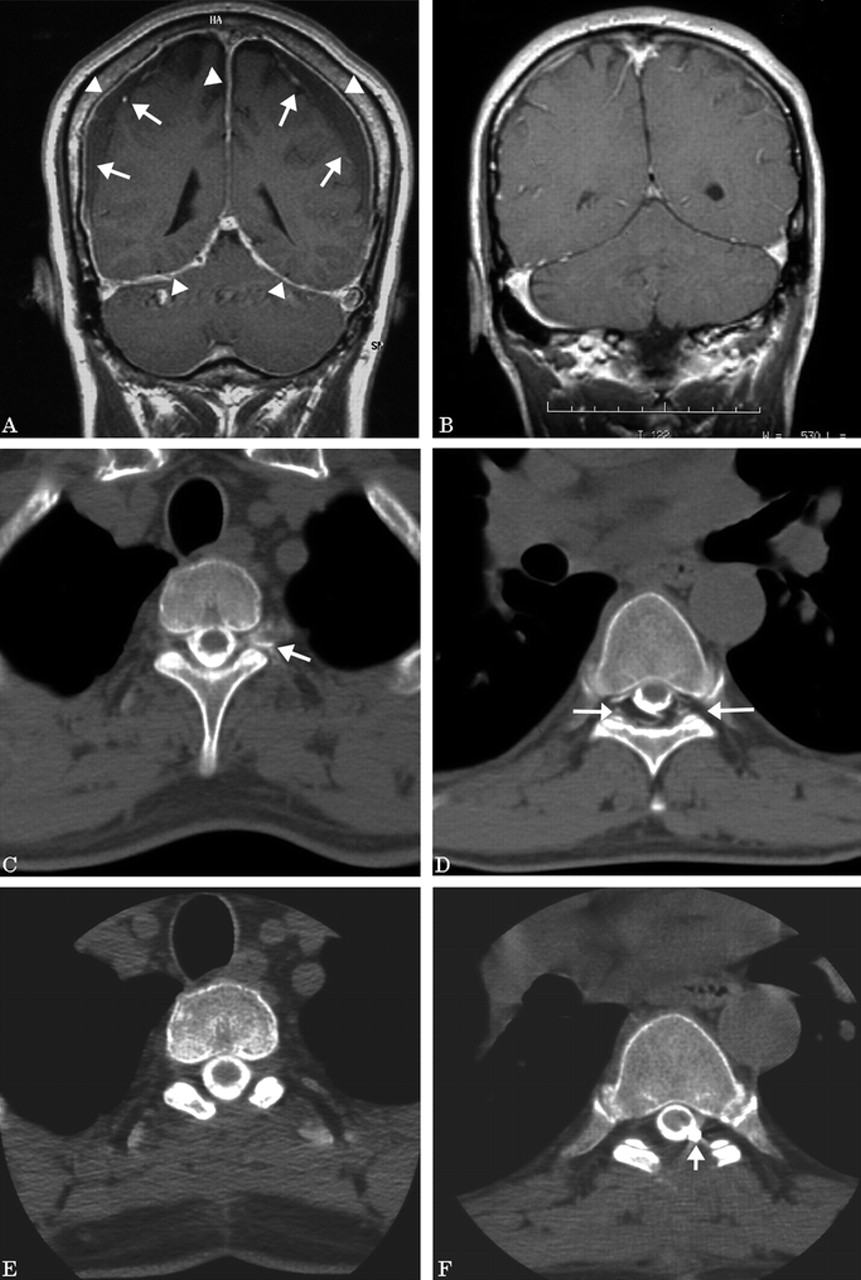

患者的临床和影像学特征进行了总结表。26(78%)的33名患者异常最初的核磁共振成像,和7例(22%)有一个正常的初始核磁共振。在24例MRI异常包括pachymeningeal增强,向下位移(松弛)大脑的17个病人,并在14个病人硬膜下流体集合。金宝搏188手机app得到一个好的结果在25 26(97%)患者异常MRI与只有1(14%)的患者7正常MRI (p= 0.00004)。患者最初的MRI是正常随访MRI研究从未开发的任何异常。所有患者正常初始核磁共振有多个脊髓CSF泄漏。这些患者接受了多种治疗干预措施包括手术用CT myelographic确认成功的所有可视化脑脊液漏的修复(图)。诊断鞘内注入生理盐水进行五的六名病人与正常MRI持久的症状。位置在四个五个病人症状解决盐水,表明存在一个持续的脑脊液漏的设置正常CT脊髓x光像。